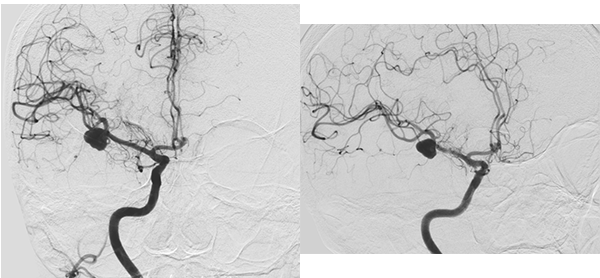

Paciente femenina de 72 años de edad con antecedentes de hipertensión arterial, dislipidemia, sobrepeso y extabaquista, a quien en contexto de estudio por hipoacusia neurosensorial se le realizó RM de cerebro y conductos auditivos internos con contraste endovenoso, en la cual se observó como hallazgo incidental lesión expansiva marcadamente hipointensa en T2 localizada a nivel temporal anterior derecho de aproximadamente 23 x 14 mm de diámetro en relación con el sector distal de la arteria cerebral media homóloga. Tras la inyección de contraste presentó refuerzo heterogéneo, con un componente de aspecto trombosado en el sector basal de la misma, asociado a extenso edema periférico (Figura 3). Se decidió realizar consulta con especialidad de neurocirugía quien sugirió completar la aproximación diagnóstica con AD de vasos intracraneanos en la cual se observó a nivel silviano derecho dilatación aneurismática de contornos lobulados con diámetros de 10.7 x 9.7mm, no presentando un cuello favorable para el acceso endovascular (Figura 4 y 5). En dicho estudio se menciona además pequeño aneurisma de 2mm en arteria comunicante anterior y otro silviano izquierdo de 4mm.

Figura 4: Estudio por AD. Tanto en la imagen de la izquierda (vista anterior) y derecha (vista lateral) se observa a nivel silviano derecho dilatación aneurismática de contornos lobulados con diámetros aproximados de 10.7 x 9.7 mm.

Figura 5: Estudio por AD, reconstrucción 3D del aneurisma descripto en Figura 4.